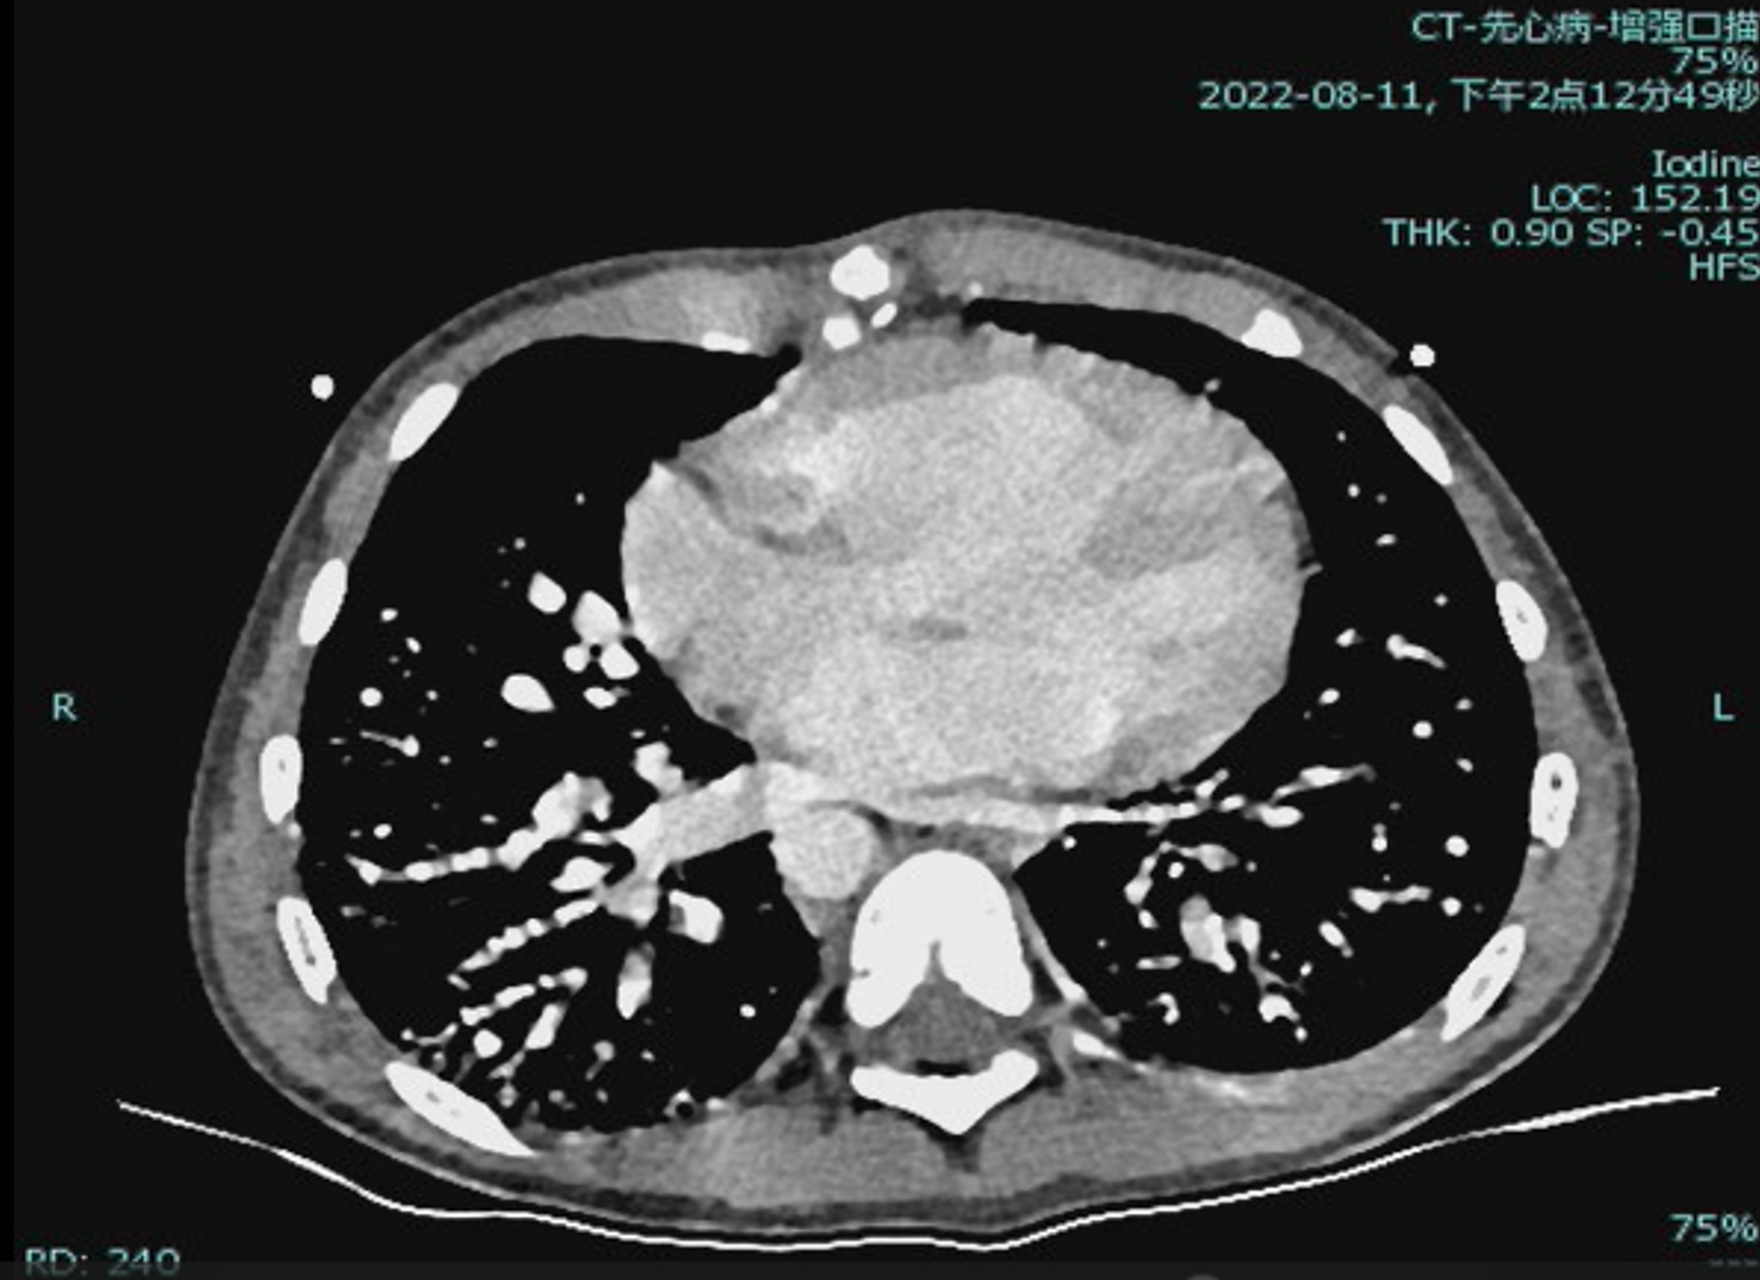

Laboratory testing showed hemoglobin 225 g/L and hematocrit 73.3%. Arterial blood gas revealed PO©ü 30.7 mmHg and SO©ü 58.1%. Chest X-ray showed cardiomegaly (cardiothoracic ratio 0.6) and increased pulmonary markings. Echocardiography demonstrated a patent Glenn anastomosis. Contrast-enhanced CT revealed absence of the main pulmonary artery and diffuse pulmonary arteriovenous malformations (PAVMs) in both lungs, most prominent in the lower lobes.